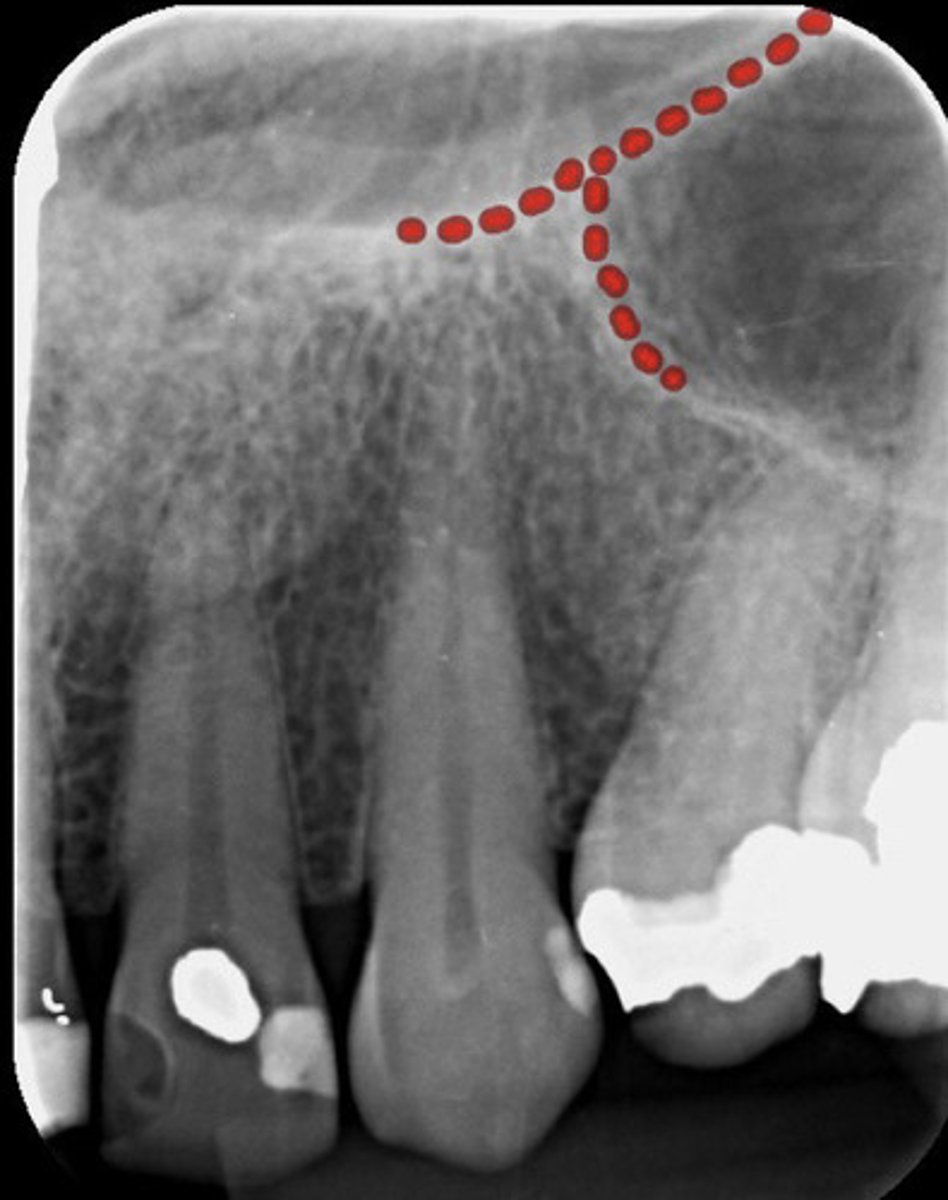

What are the red dots representing?

Hypercementosis